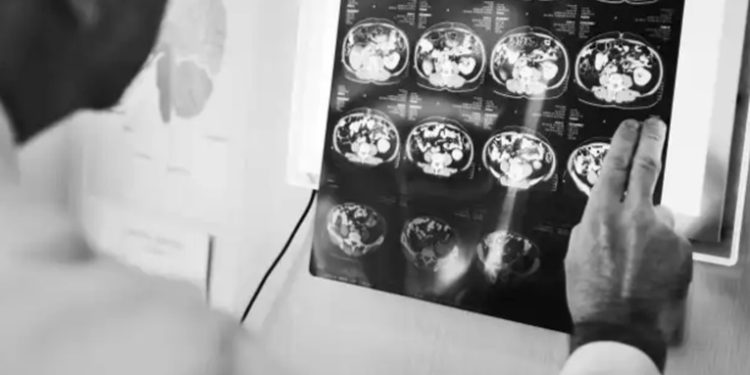

El ministerio de salud pública dio a conocer que se detectaron al menos 39 casos de una enfermedad neurológica con síntomas parecidos al síndrome Guillain Barre, que afecta directamente al sistema nervioso.El padecimiento neurológico por el que el Ministerio de Salud emitió una alerta el fin de semana, podría generarse por mala higiene e ingesta de alimentos contaminados afirmó el epidemiólogo Erwin Calgua.

El ministerio de salud pública dio a conocer que se detectaron al menos 39 casos de una enfermedad neurológica con síntomas parecidos al síndrome Guillain Barre, que afecta directamente al sistema nervioso.

El padecimiento neurológico por el que el Ministerio de Salud emitió una alerta el fin de semana, podría generarse por mala higiene e ingesta de alimentos contaminados afirmó el epidemiólogo Erwin Calgua.